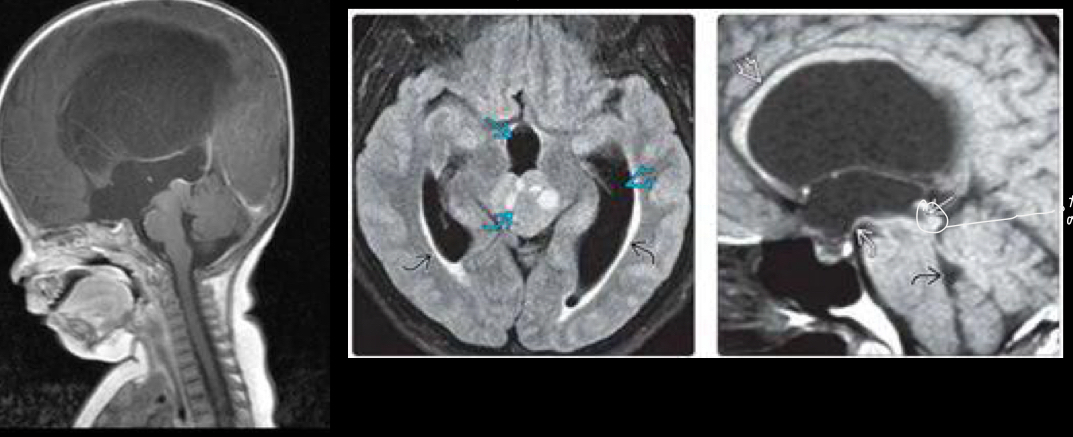

imagen para no comunicante

A

RM

TC

USG

q se ve en RM no comunicante

dilatación proximal a la obstrucción

NO comunicante

Intraventricular

Estenosis acueducto de Silvio